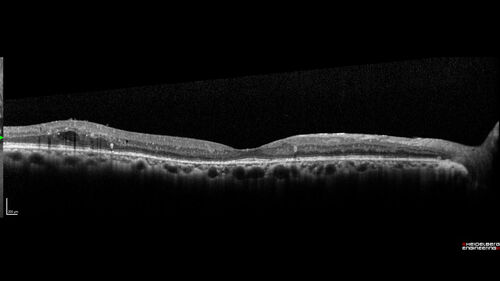

Severe NPDR with non-perfusion on FA

64 year old man with 20/32 vision in both eyes and mild blurring. FA shows non-perfusion but no proliferation